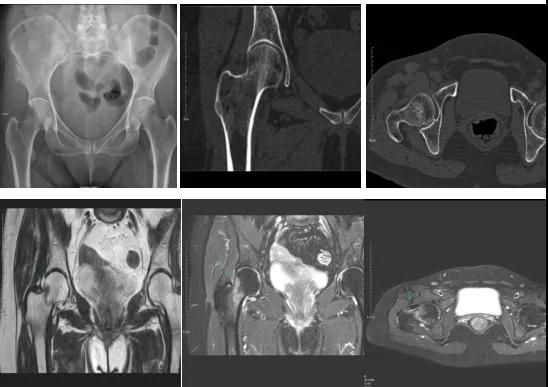

2.CT或MRI檢查。CT是斷面成像,不會(huì)出現(xiàn)重疊而導(dǎo)致漏診,同時(shí)CT還可以進(jìn)行多平面的重建,除了發(fā)現(xiàn)X線無(wú)法發(fā)現(xiàn)的骨折外,還可以三維直觀的顯示骨折的程度,對(duì)臨床治療有指導(dǎo)意義。CT無(wú)法發(fā)現(xiàn)骨裂、不全骨折或者骨挫傷,對(duì)軟組織的損傷診斷也有局限性,MRI就可以發(fā)現(xiàn)這些損傷。

DR示:右側(cè)股骨頸未見(jiàn)明顯骨折征象。CT右側(cè)股骨頸骨質(zhì)密度不均。患者體征明顯,為明確診斷,行MRI檢查。MRI示:右側(cè)股骨頸T1WI呈低信號(hào),脂肪抑制序列呈高信號(hào);提示右側(cè)股骨頸隱匿性骨折。